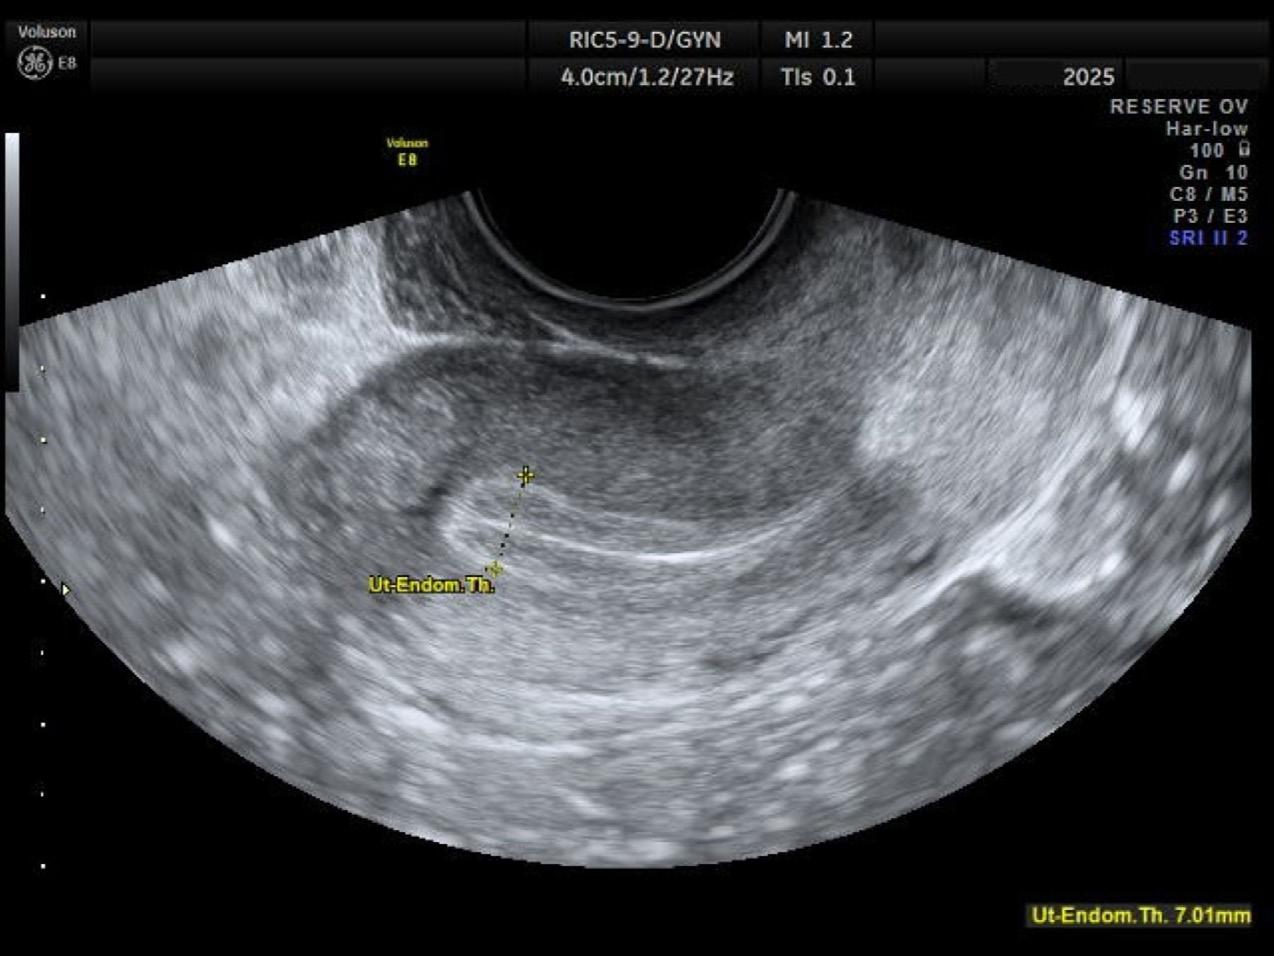

L’échographie de cycle

Monitorage de l’épaisseur et de l’allure de l’endomètre ainsi que de la taille des follicules. Pour l’endomètre, on cherche un endomètre d’allure trilaminaire (Figure 2) d’environ 7 mm d’épaisseur. On cherche à savoir si un éventuel embryon peut aller y faire son nid. C’est une information très pertinente pour les inséminations et les transferts d’embryon. Pour les follicules, on examine des follicules dominants, puisque ceux-ci seront responsables de libérer les ovules matures